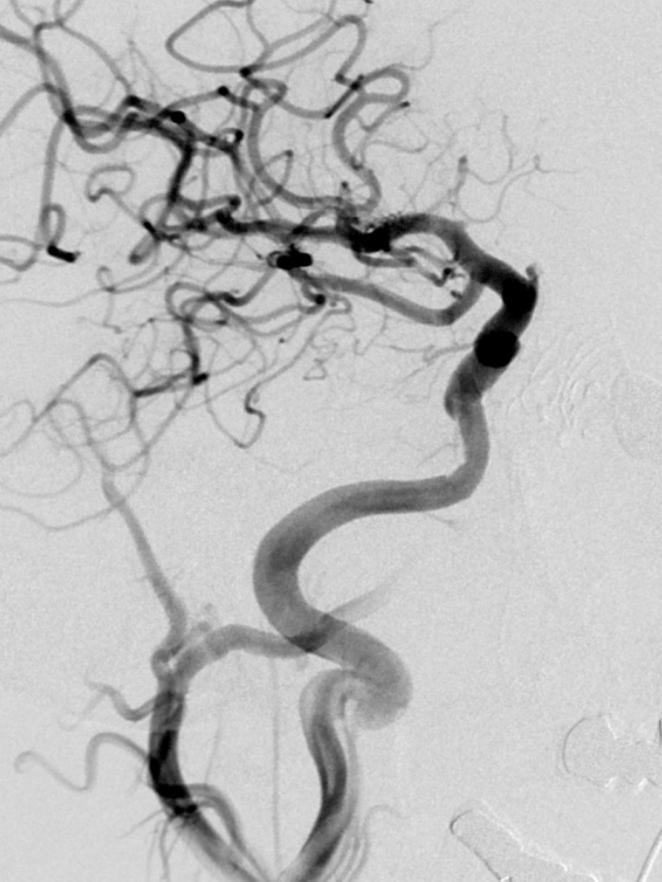

Acute endovascular repair of iatrogenic right internal carotid arterial laceration.

Carotid arterial bleeding is a feared and possible life-threatening complication of transsphenoidal surgery. We present a case of a meningioma that during resection had a serious complication with laceration of the internal carotid artery (ICA). These patients rarely undergo endovascular treatment, with indications mainly due to the development of pseudoaneurysms or penetrating trauma. However, endovascular treatment with covered stents of carotid arterial bleedings is a feasible alternative due to technical advances and smaller sized stentgrafts that expand treatment options.

颈动脉出血是经蝶窦手术令人恐惧且可能危及生命的并发症。我们报告一例脑膜瘤病例,该病例在切除过程中出现严重并发症,导致颈内动脉(ICA)撕裂。这些患者很少接受血管内治疗,其适应症主要是由于假性动脉瘤的形成或穿透性创伤。然而,由于技术进步以及尺寸更小的覆膜支架拓宽了治疗选择,采用覆膜支架对颈动脉出血进行血管内治疗是一种可行的替代方法。